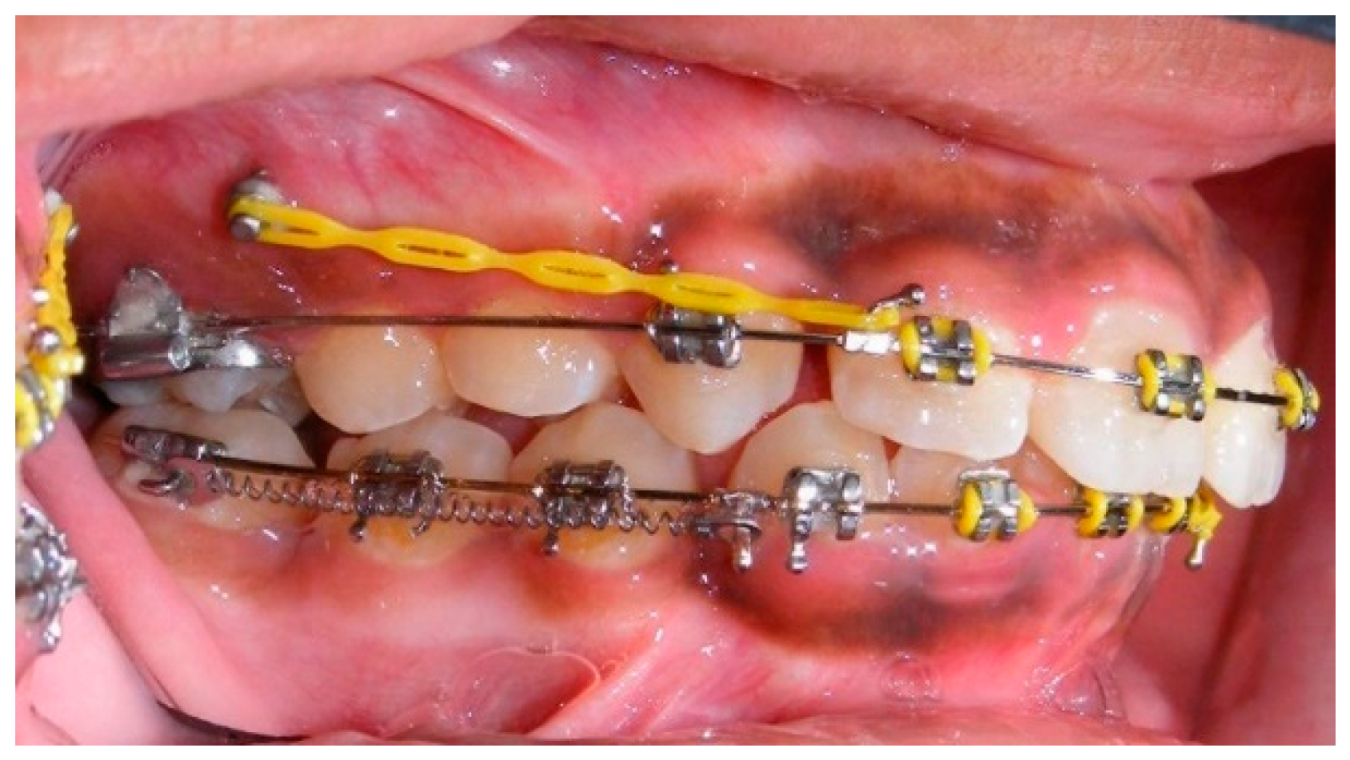

- Assessment of proposed sites of temporary anchorage device (TAD). Figure 11, Figure 12, Figure 13 and Figure 14 show correction of the Class II molar relationship using a temporary anchorage device. Figure 11 shows a pre-treatment intraoral photograph of the right side. The Class II molar relationship can be observed. Figure 12 shows coronal, sagittal and axial views, as well as a volume rendering of CBCT that was acquired in order to assess the site of the temporary anchorage device. Figure 13 shows an intraoral photograph of the right side, in which the TAD was placed mesial to the maxillary first molar, and a power chain was attached from this TAD to a hook placed distal to the lateral incisor. Figure 14 shows a post-treatment intraoral photograph showing improvement of the Class II molar relationship after removal of all orthodontic appliances.